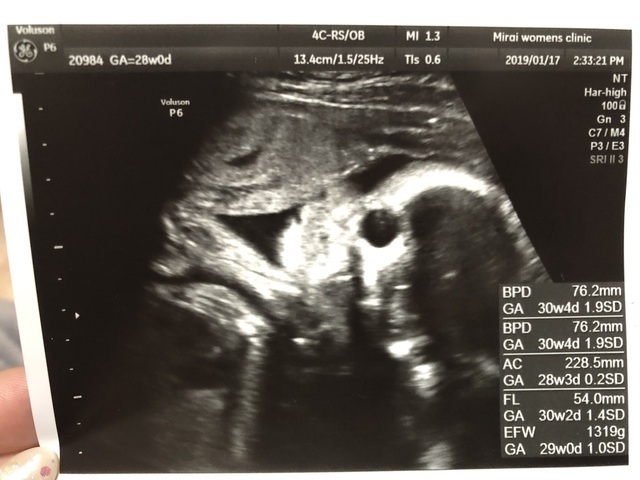

29週0日(29w0d・女の子)|みちゃこ88 さん(28歳)

エコー写真撮影時のエピソード:

初めて顔がはっきり見えました!小さいと言われてて心配だったけど、ぷっくりしてきて安心しました。

でも膀胱炎になってしまってたくさん水分を取るようになったのでトイレが近くて夜何回も起きてしまいます( ; _ ; )がんばって乗り越えよう!